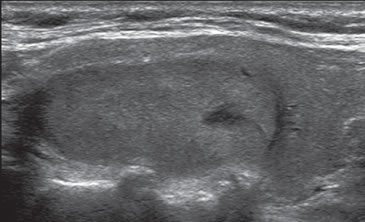

Son tumores sólidos, únicos, iso o hiperecogénicos, muy homogéneos, encapsulados, de contornos lisos, de forma ovoidea, sin microcalcificaciones (Figura 3b). En el 80% de los casos se puede observar un halo hipoecogénico. Ocasionalmente pueden ser discretamente hipoecogénicos. La vascularización habitualmente esta aumentada en la periferia con vasos que se descuelgan hacia el centro de la lesión (Figura 12). A diferencia de los nódulos coloideos generalmente no se observan imágenes quísticas (Figura 32).

En este grupo se encuentran principalmente las neoplasias foliculares benignas (adenomas) o malignas (carcinomas). Están compuestos de células foliculares o células de Hurthle en distinta proporción, y son encapsuladas. La mayoría (85%) corresponden a adenomas foliculares. Sin embargo, con el mismo patrón se puede presentar el carcinoma folicular bien diferenciado, aunque este suele ser de mayor tamaño, hipoecogénico, de contenido más heterogéneo, la capsula de mayor espesor (Figura 33a y b) y el aumento de la vascularización es difuso22. La presencia de calcificaciones intranodulares conlleva mayor riesgo de malignidad.